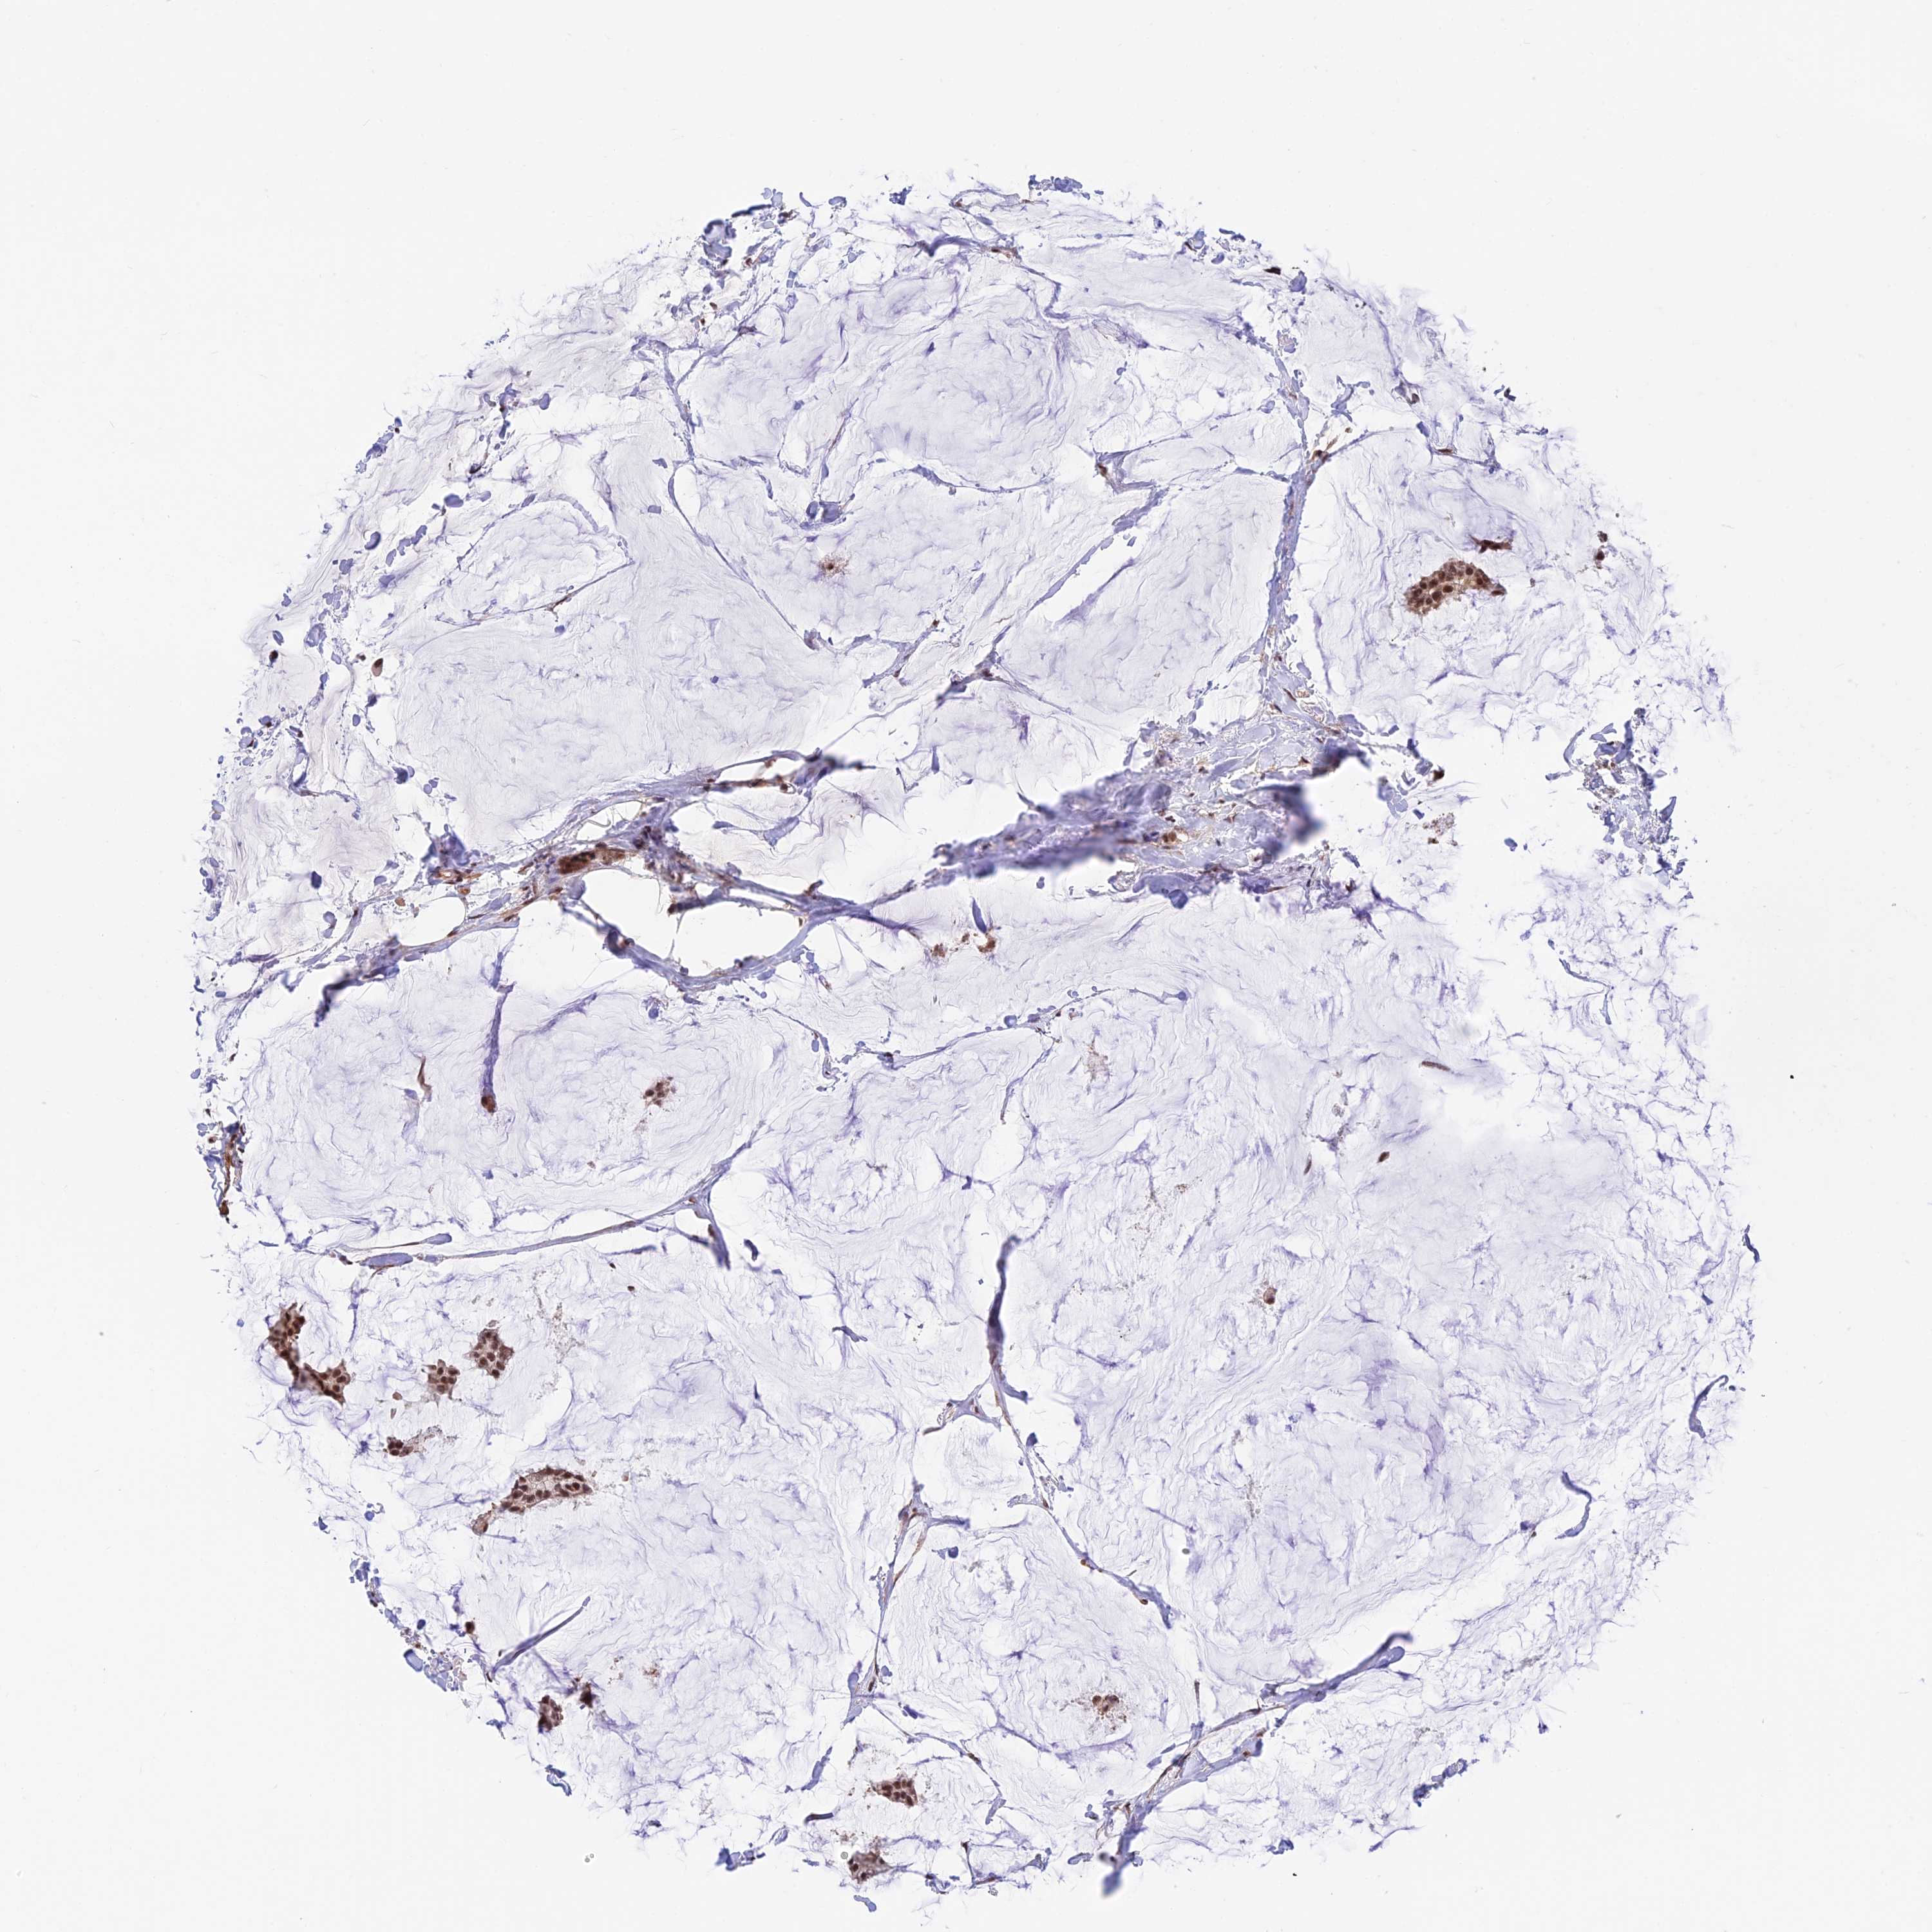

CANCER BREAST CANCER Show tissue menu

BRCA TCGA BRCA VALIDATION PROTEIN EXPRESSION

Breast cancer

Human cancer